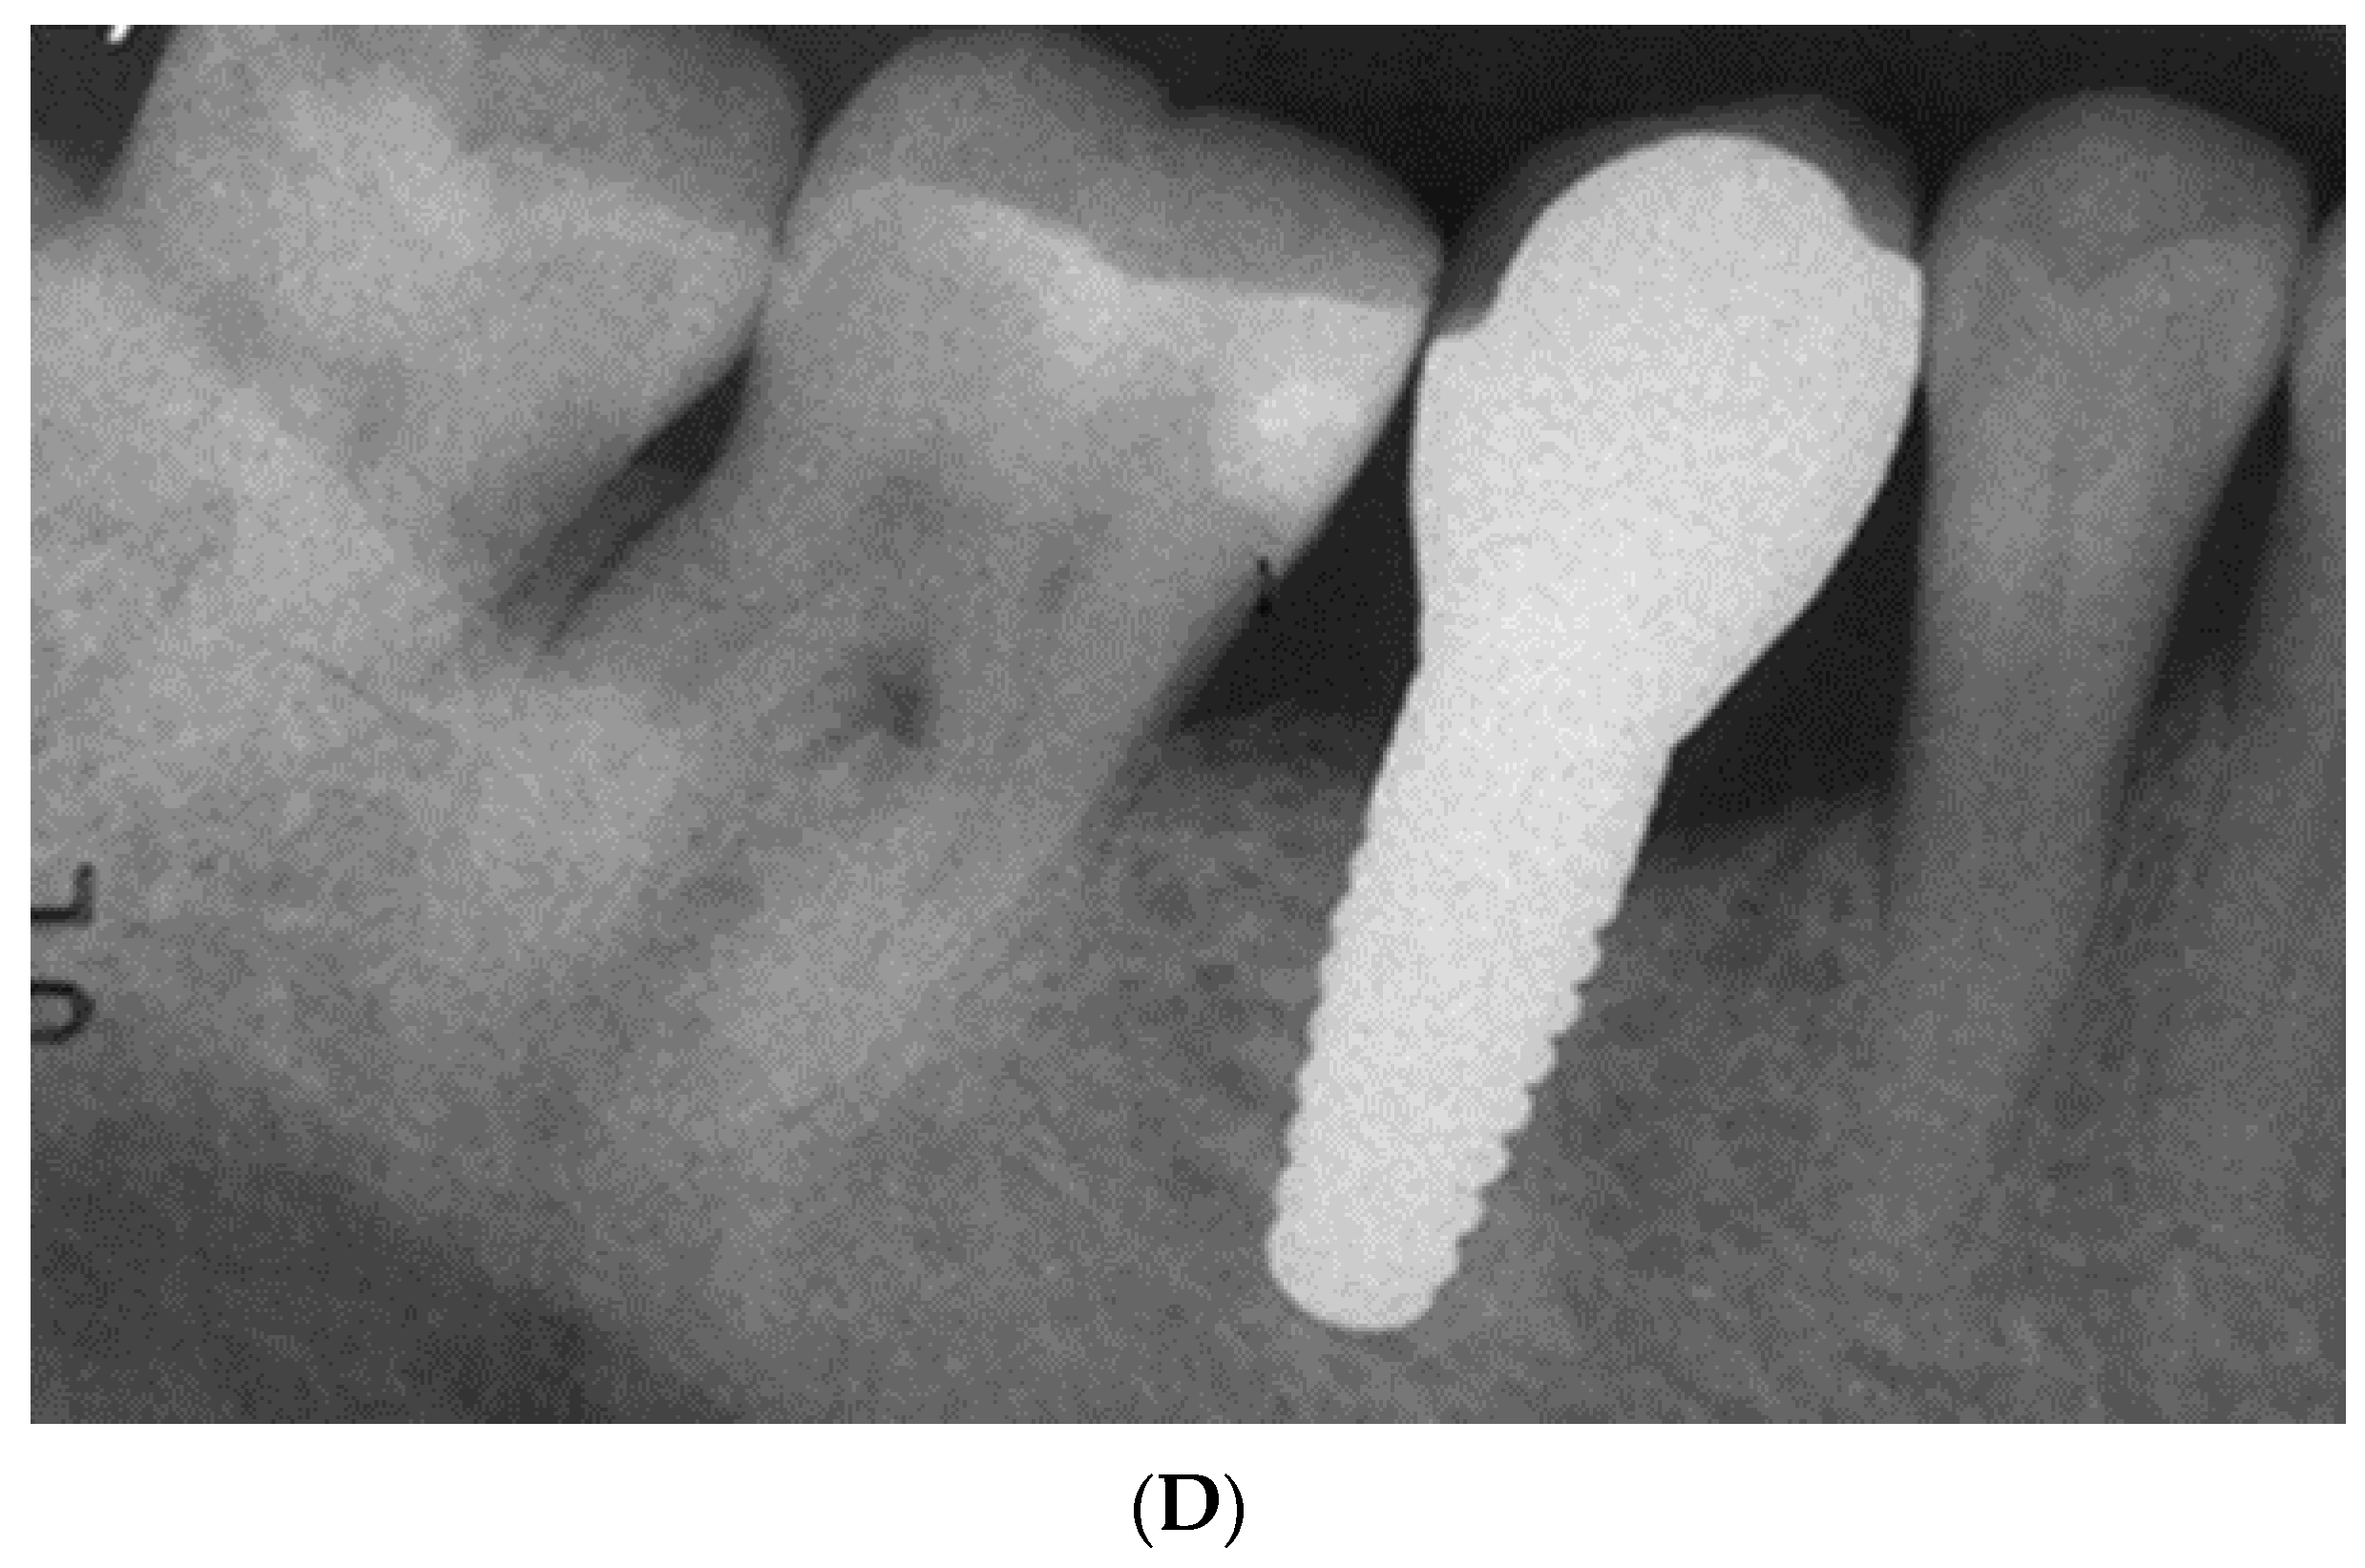

- Pirker, W.; Kocher, A. Immediate, non-submerged, root-analogue zirconia implant in single tooth replacement. Int. J. Oral Maxillofac. Surg. 2008, 37, 293–295. [Google Scholar] [CrossRef]

- Pirker, W.; Kocher, A. Immediate, non-submerged, root-analogue zirconia implants placed into single-rooted extraction sockets: 2-year follow-up of a clinical study. Int. J. Oral Maxillofac. Surg. 2009, 38, 1127–1132. [Google Scholar] [CrossRef]

- Mangano, F.G.; De Franco, M.; Caprioglio, A.; Macchi, A.; Piattelli, A.; Mangano, C. Immediate, non-submerged, root-analogue direct laser metal sintering (DLMS) implants: A 1-year prospective study on 15 patients. Lasers Med. Sci. 2014, 29, 1321–1328. [Google Scholar] [CrossRef]

- Akkoyun, E.F.; Demirbas, A.E.; Gumus, H.O.; Alkan, B.A.; Alkan, A. Custom-made root analog immediate dental implants: A prospective clinical study with 1-year follow-up. Int. J. Oral Maxillofac. Implants 2022, 37, 1223–1231. [Google Scholar] [CrossRef]